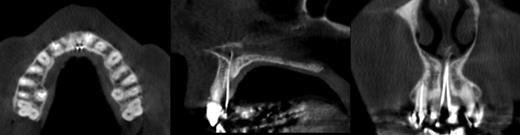

Clinical examination revealed two small mucosal openings on either side of the incisive papilla, which could be probed partially (Fig. 1). Palpation of this area was painful. Two gutta-percha points were inserted into the two openings (Fig. 2). The cone beam computed tomography (CT) confirmed two patent NDPs with oronasal communication (Fig. 3).

Gutta-percha points in the two NPDs showing communication between the oral and nasal cavities (cone beam CT: axial, sagittal and coronal sections).